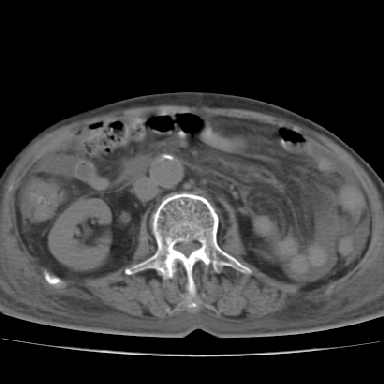

以下是引用qian在2006-12-4 19:11:00的发言:[br]胸腔和腹腔内均见有液性影,肝上极包膜下有一较大椭圆形低密度影,密度均匀,边缘清晰,结合病史考虑术后肝脓肿并胸腹腔积液。

以下是引用chry3在2006-12-4 21:05:00的发言:[br]应该往上扫几层,我考虑膈下脓肿。[br]大家考虑:胃部手术怎会造成肝内脓肿,隔下脓肿到是会造成的

以下是引用dyqct在2006-12-4 19:54:00的发言:[br]考虑:1、肝包膜下脓肿;[br] 2、少量腹水;[br] 3、右侧少量胸膜腔积液。